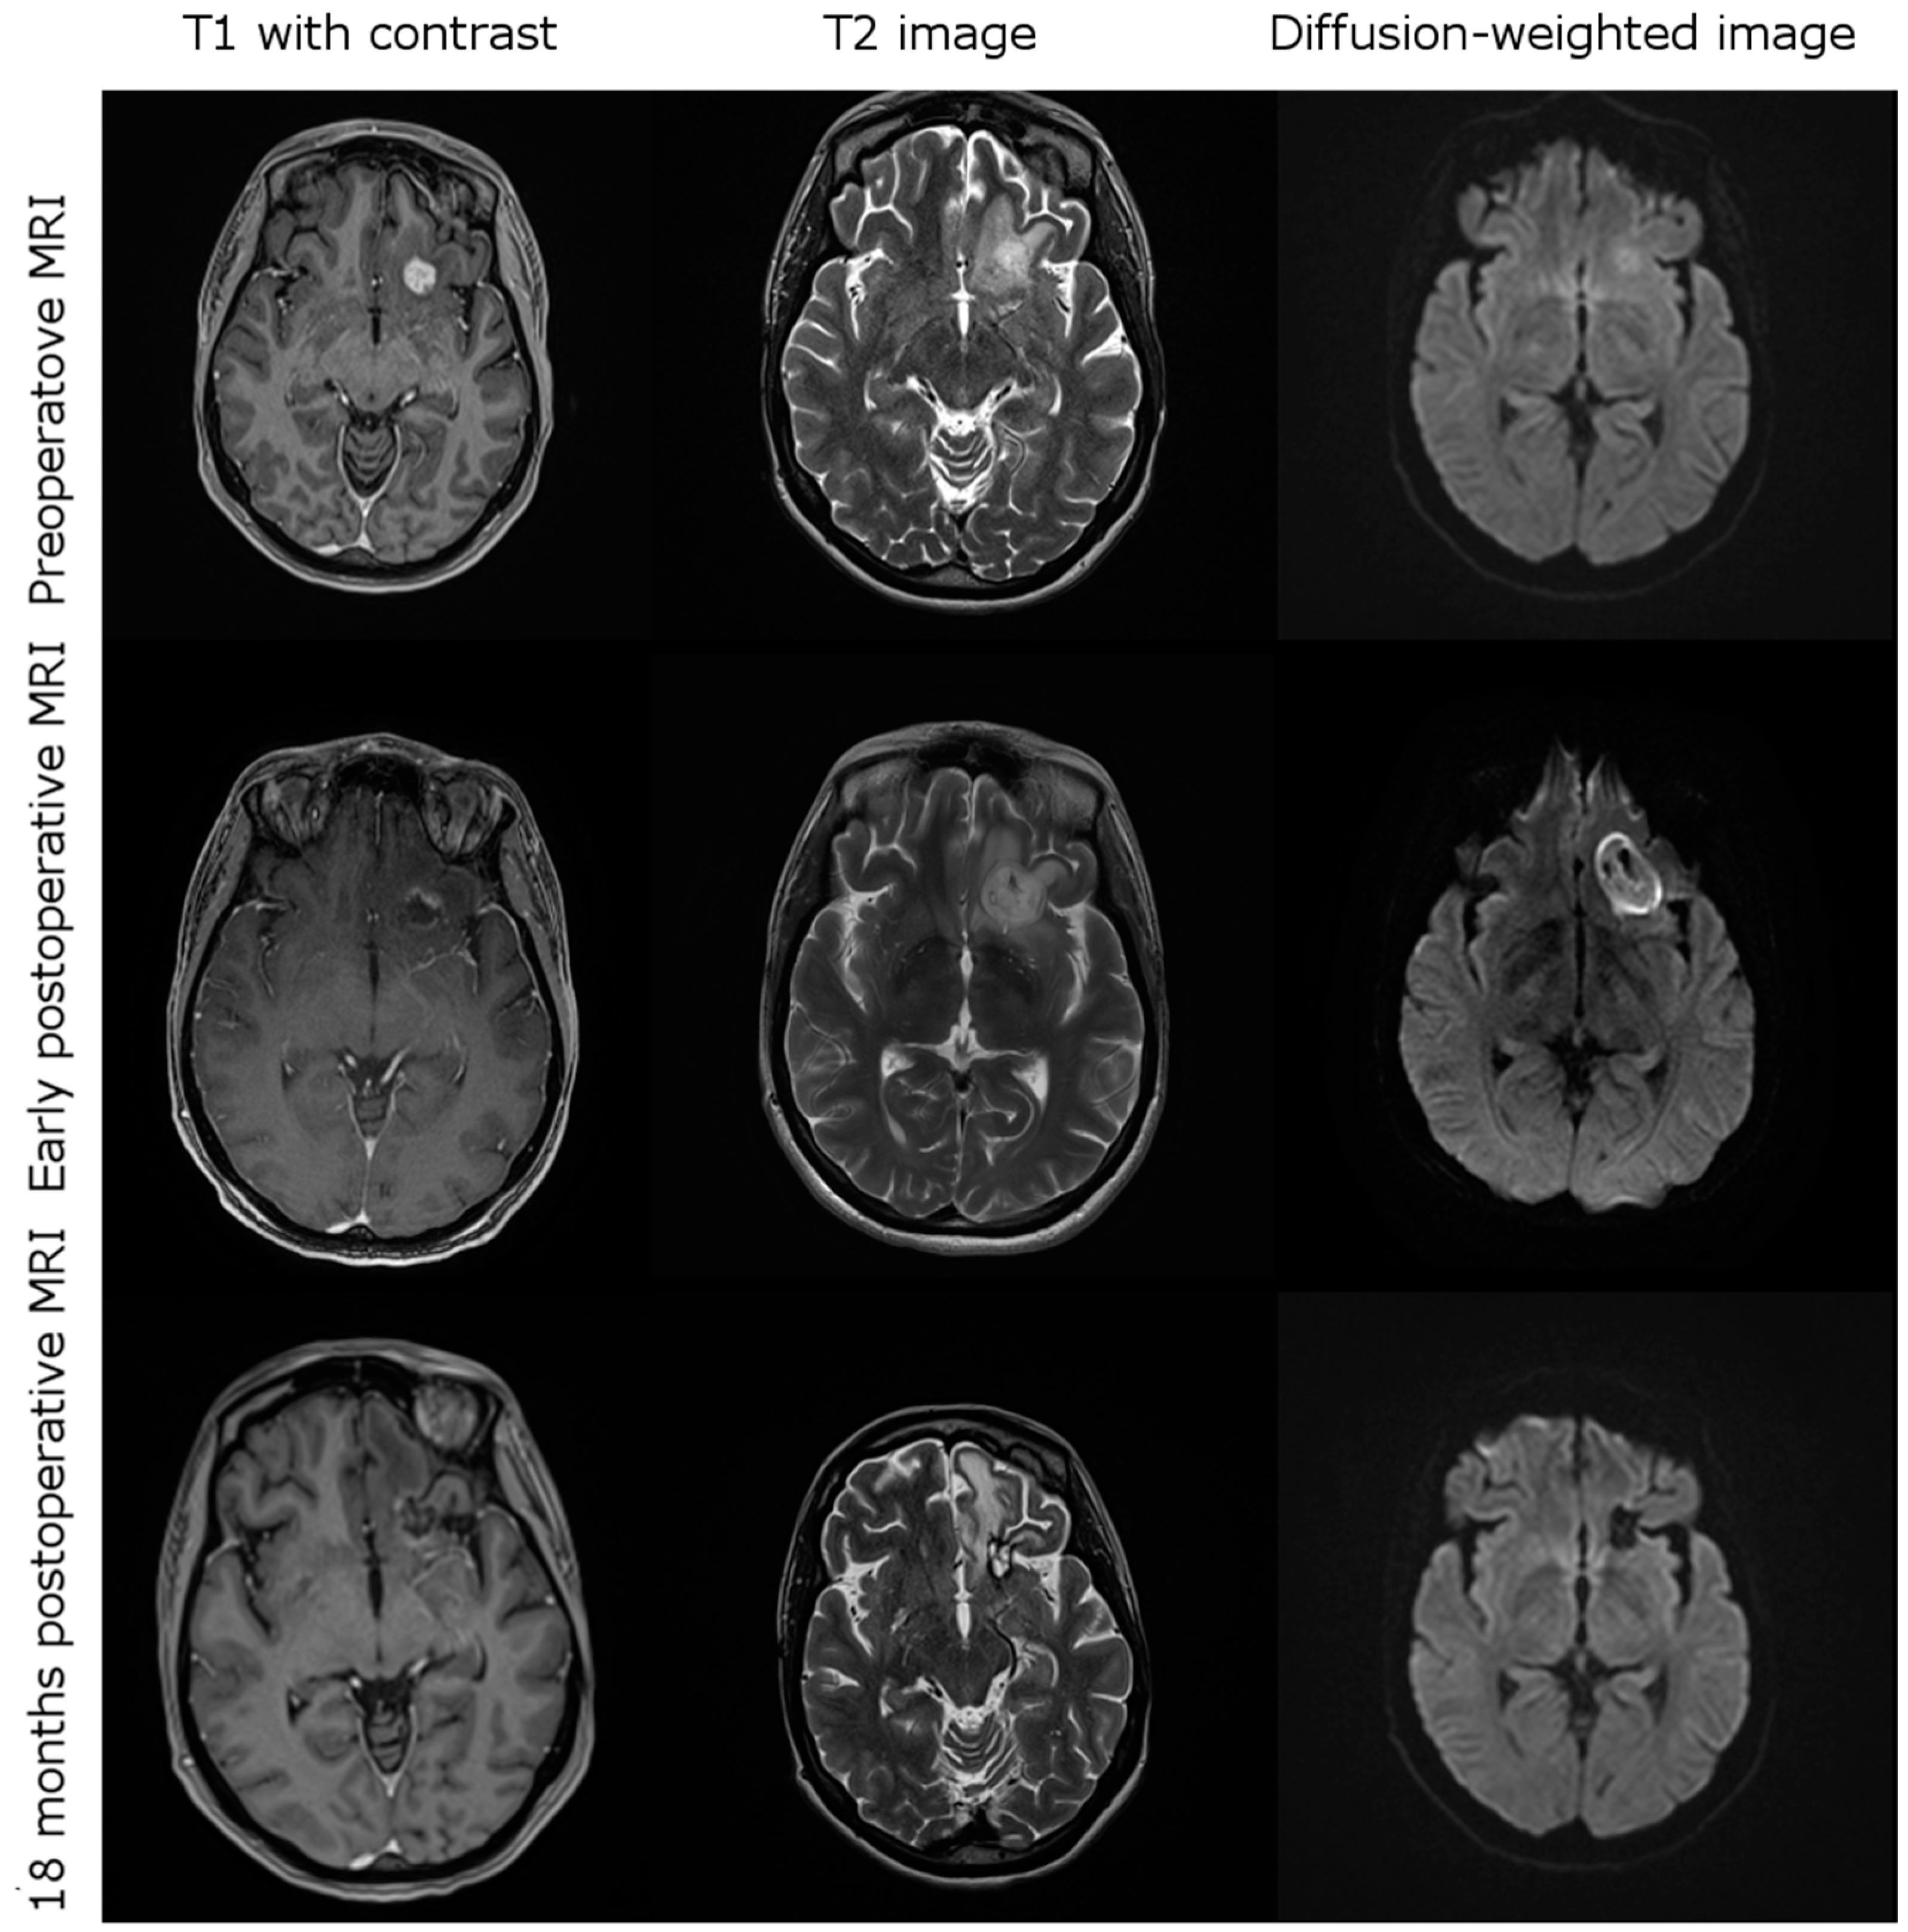

3.3. Imging after iPDT